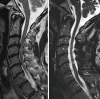

Cervical laminoplasty is a non-fusion, decompression procedure for cervical spondylotic myelopathy (CSM). It is most commonly indicated for patients with multilevel stenosis who have preserved sagittal alignment and minimal to no axial neck pain related to spondylosis. Expansion of the laminar arch can allow for direct and indirect decompression of the spinal canal. Relative contraindications include those patients with significant preoperative neck pain, kyphotic alignment and substantial instability. Potential advantages over laminectomy and fusion include avoiding fusion-related complications, and the preservation of motion. Important technical considerations include meticulous extensor muscle management, with special attention being given to preserving the soft tissue attachments to C2. In the properly selected patient, outcomes are comparable, and in some studies superior, to other operations for CSM.